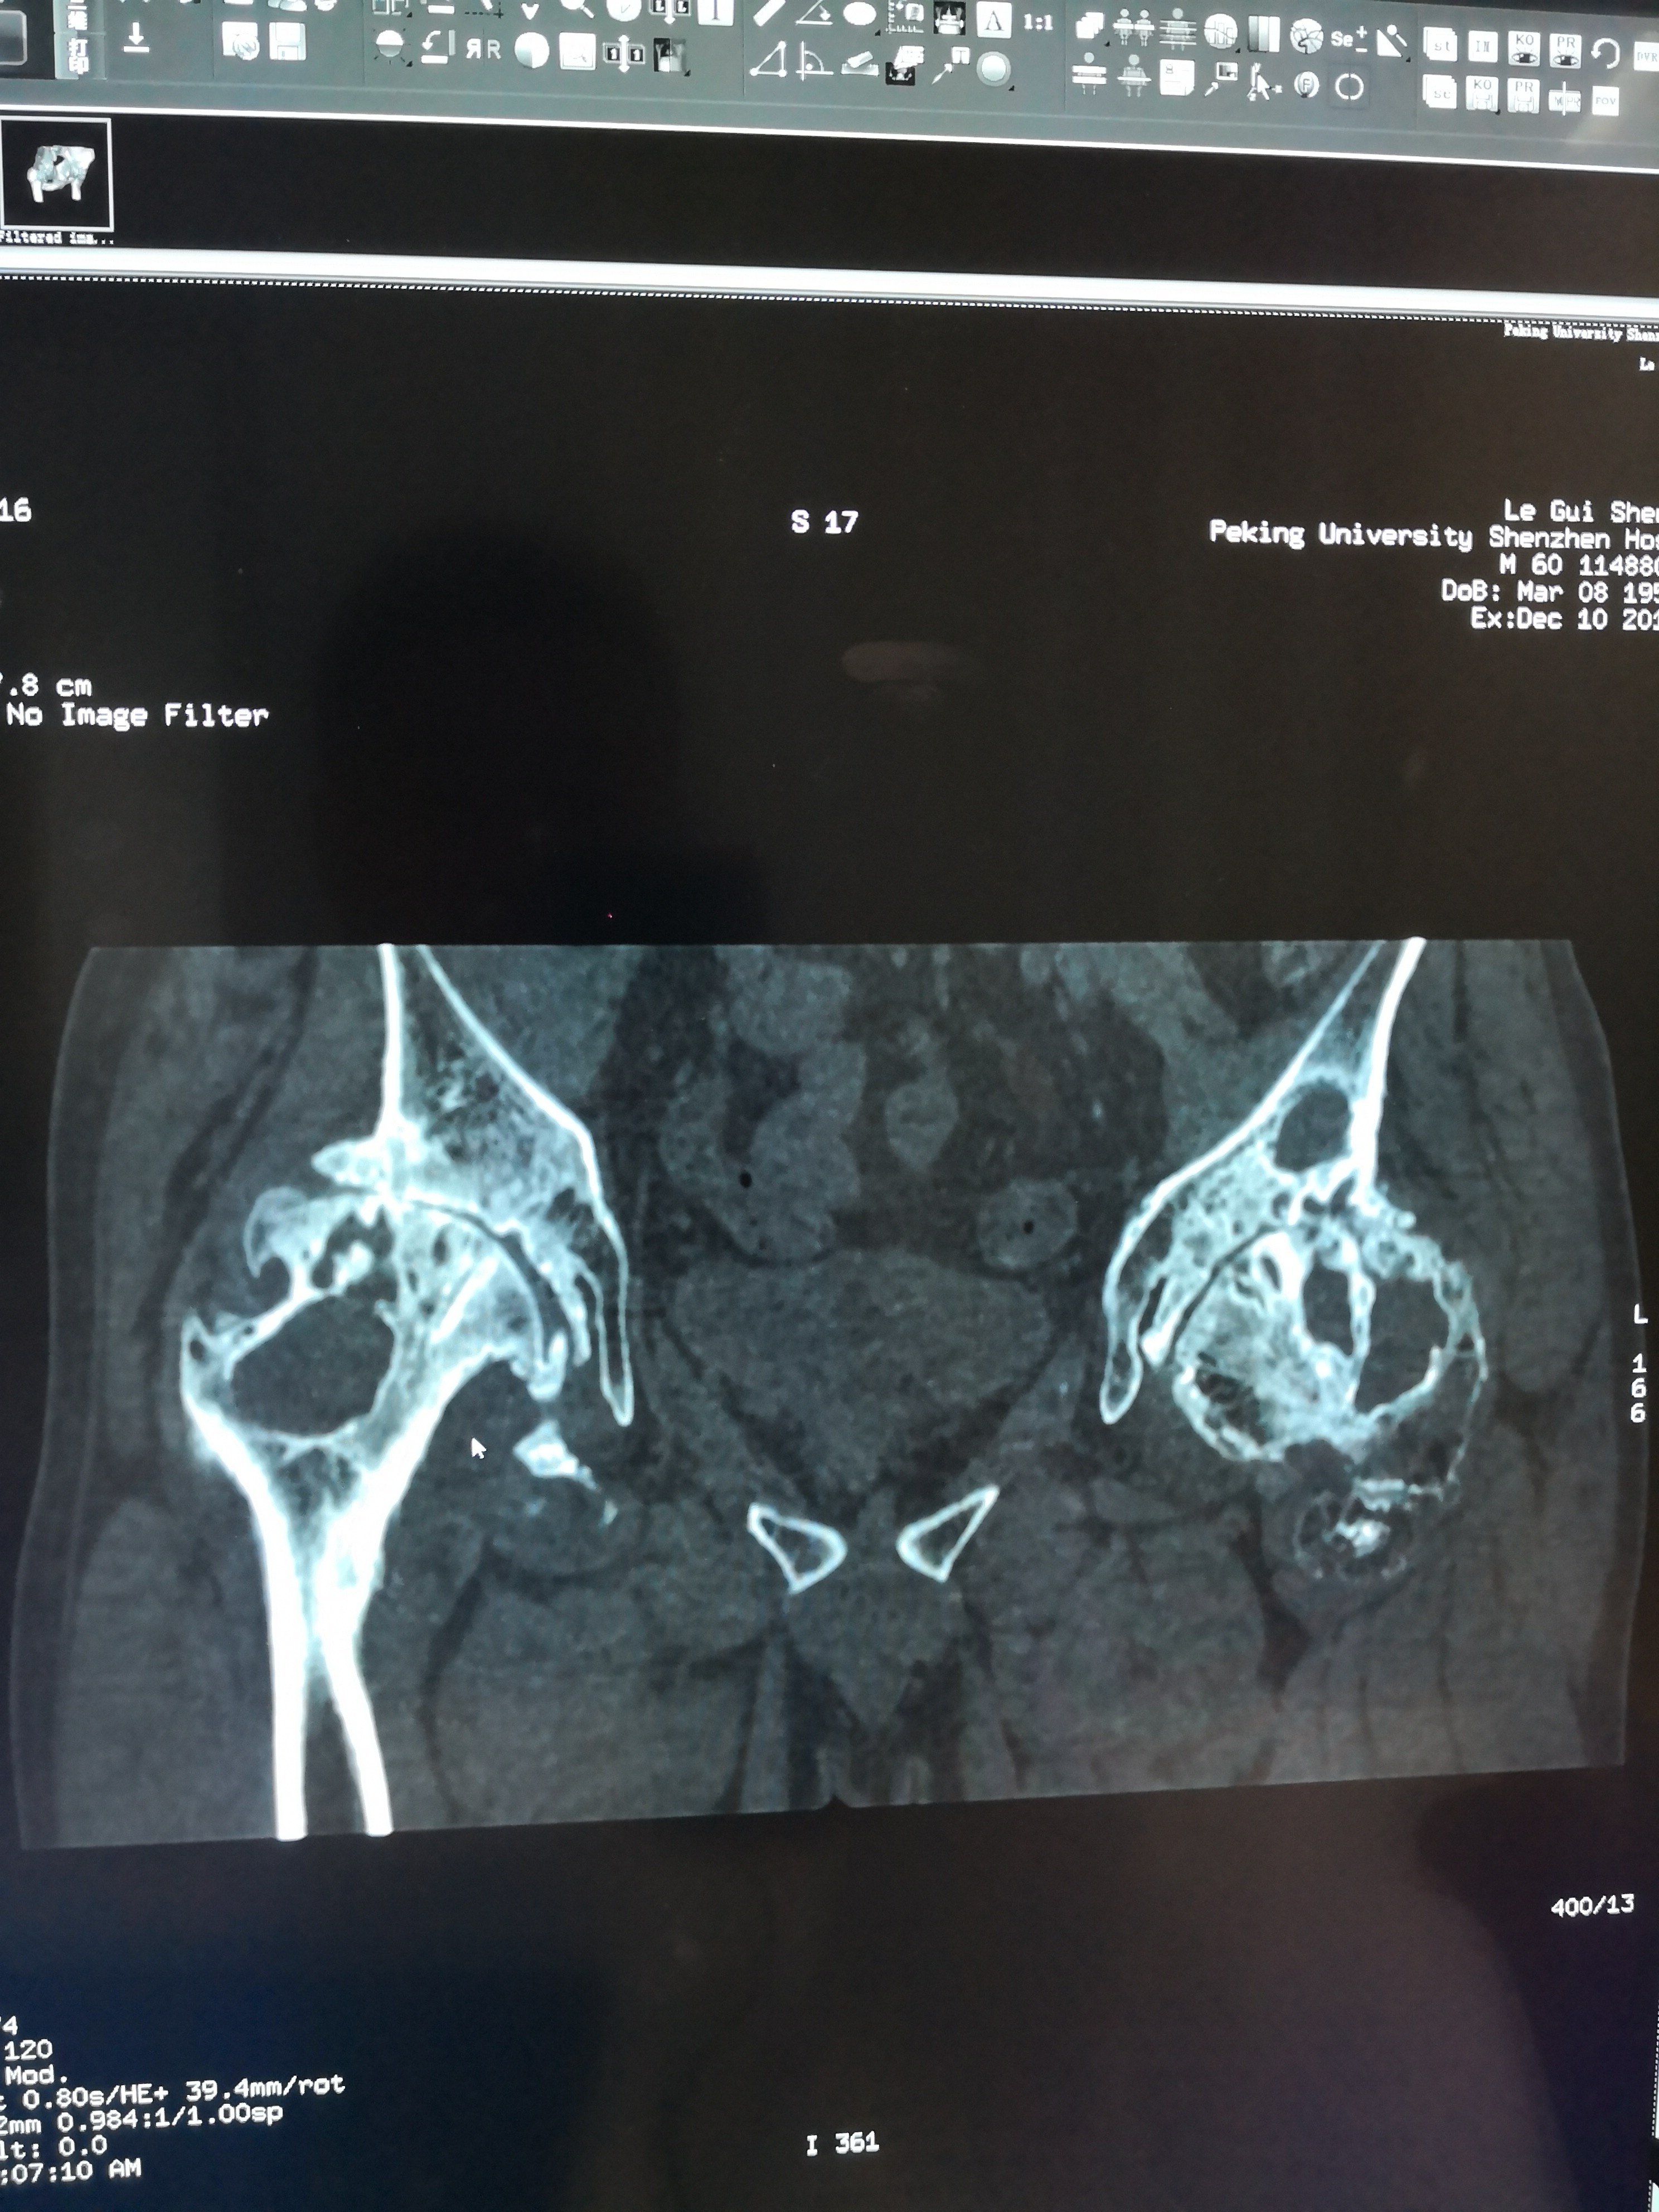

患者60岁,抽烟(每天2包)及外伤导致双侧股骨头坏死30余年。但一直未做治疗,近期疼痛加重,行走跛行,双下肢不等长,双髋关节外展受限。住院后给予双侧腹股沟区内收肌松解术,并行双侧全髋关节置换术。术中见髋臼严重增生,股骨头变形呈蘑菇状,股骨近端硬化,髓腔消失,被硬化骨全覆盖。髋臼侧卵圆窝消失,被增生骨覆盖。髋臼边缘增生明显。去除大量增生骨,给予再造髋臼及股骨近端成型术,顺利完成双侧髋关节置换手术。术后病人恢复良好。术后三天可以去除助行器自己行走。